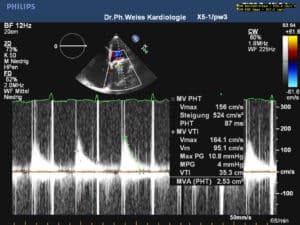

Hier eine Doppler Messung duch diese Klappe: